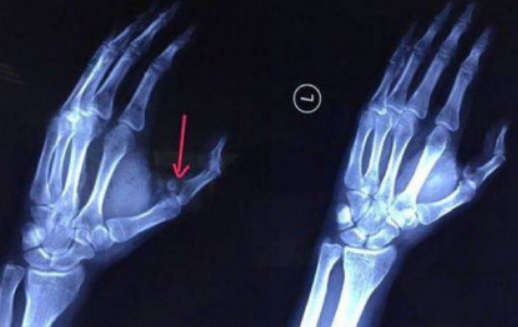

20歲的小袁是長沙某高校大三學生,暑假在長沙租房,為出國進行外語培訓。7月29日晚餐前,小袁和往常一樣,從出租房冰箱里拿出一瓶可樂準備喝,結果不小心將塑料可樂瓶掉在地上。就在他撿起來打開瓶蓋的瞬間,可樂瓶突然發生爆炸,將他的左手虎口處炸開一條約7cm長的口子。劇烈疼痛讓小袁發出慘叫,家人聞訊趕來,發現小袁傷口血流不止,受傷的左手也動彈不得,隨即將他送往湖南省人民醫院急診一科就診,醫生為其傷口進行緊急處理。X 光檢查發現,小袁左手拇指近節指骨骨折,需進行手術固定,于是將他收入創傷骨病科病房。術后,小袁左手需采用石膏固定4~6周。